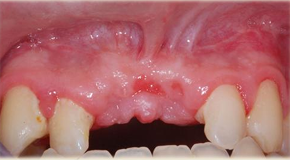

• L’importanza del tessuto cheratinizzato in implantologia

• Tecniche di aumento tessuti molli perimplantari

• Approfondimento di fornice